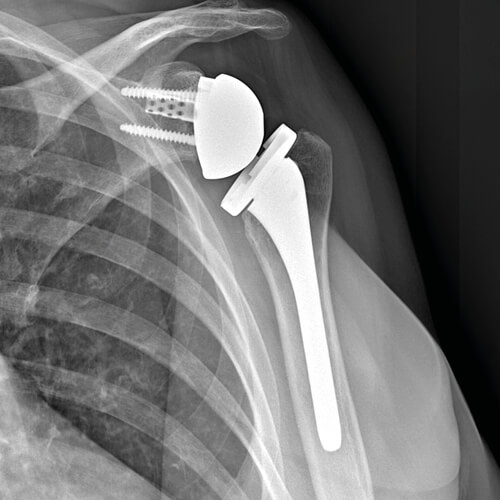

La protesi della spalla può essere di due tipi, anatomica o inversa.

- La protesi anatomica è indicata nei casi in cui la cuffia dei rotatori risulti integra. La testa dell’omero e la cavità glenoidea vengono sostituite da componenti che simulano la normale anatomia e meccanica dell’articolazione.

- La protesi inversa viene impiantata quando la cuffia dei rotatori è danneggiata. Si parla di protesi inversa perché utilizza componenti non anatomiche: la testa dell’omero viene sostituita da una componente concava, mentre la cavità glenoidea viene sostituita da un’emisfera. L’inversione permette il movimento del braccio grazie al muscolo deltoide, anche senza l’uso della cuffia dei rotatori.